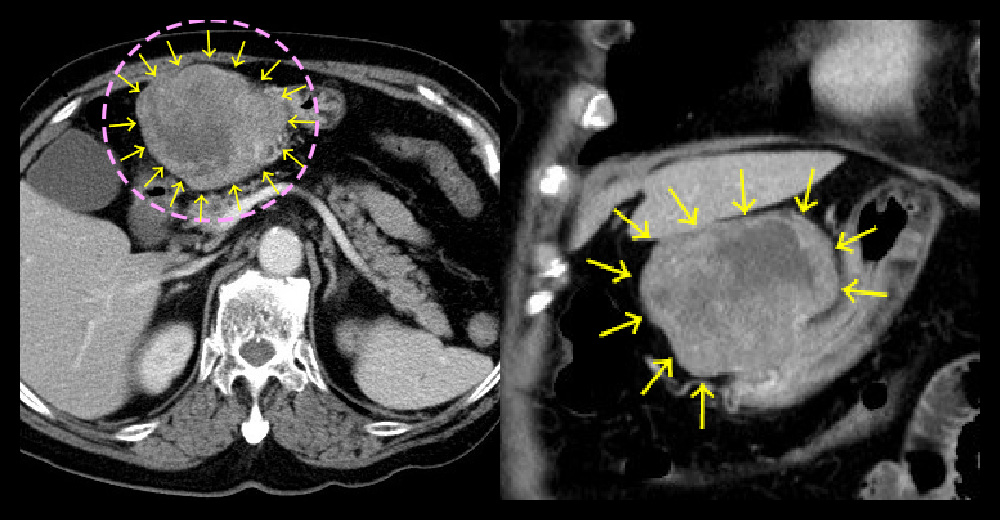

胃GIST~CT

左から 造影CT 門脈相・水平断 / 造影CT 門脈相・冠状断